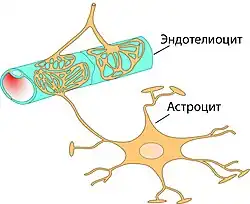

Основным элементом структуры ГЭБ являются эндотелиальные клетки. Особенностью церебральных сосудов является наличие плотных контактов между эндотелиальными клетками. В структуру ГЭБ также входят перици́ты и астроци́ты[23]. Межклеточные промежутки между эндотелиальными клетками, перицитами и астроцитами — нейроглии , меньше, чем промежутки между клетками в других тканях организма. Эти три вида клеток являются структурной основой ГЭБ не только у человека, но и у большинства позвоночных[28][29].

Эндотелий

Капиллярные сосуды выстланы эндотелиальными клетками. Эндотелий сосудов большинства тканей содержит открытые промежутки (фенестра́ции) диаметром около 50 нм и межклеточные щели от 100 до 1000 нм. Через эти промежутки вода и растворённые в ней вещества циркулируют между кровью и межклеточным пространством. Отличительной особенностью сосудов центральной нервной системы является отсутствие как фенестраций, так и межклеточных щелей между эндотелиальными клетками[30]. Таким образом, эндотелиальная выстилка капилляров мозга является сплошной[31].

Астроциты

Астроциты — большие нейроглиальные клетки звёздчатой формы. Своими отростками они выстилают стенки мозговых капилляров со стороны мозговой ткани. В то же время, несмотря на то, что пластинчатыми окончаниями их клеточных отростков выстлано около 99 % капиллярных сосудов, астроциты не выполняют прямой барьерной функции[29][74]. Астроциты тесно взаимодействуют с эндотелиальными клетками. Между ними осуществляется постоянный обмен веществ[75]. Астроглиальные клетки индуцируют возникновение и формирование ГЭБ. При проведении экспериментов по пересадке сосудов мозга в периферические органы и наоборот — периферических сосудов в ткань головного мозга, отмечено формирование ГЭБ в периферических сосудах, пересаженных в мозг (образование плотных контактов, перестройка эндотелиальных клеток), и разобщение эндотелиальных клеток и появление фенестраций между ними при пересадке мозговых сосудов[23][76]. Также in vitro показано влияние астроцитов на фенотип эндотелия. В клеточной культуре, содержащей астроциты и эндотелиоциты, отмечено более плотное расположение эндотелия по сравнению с его чистой клеточной культурой[77].